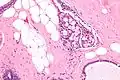

Collagenous spherulosis is characterized by a tubular/cribriform architecture with intratubular eosinophilic material that classically is arranged like the spokes of a wheel ("radial spikes"). There is usually no mitotic activity, and two cells populations (epithelial & myoepithelial) are present, like in benign breast glands.

The lesions are typically small (less than 50 spherules per lesion, less than 100 micrometers in size) and may be multifocal.

High mag.